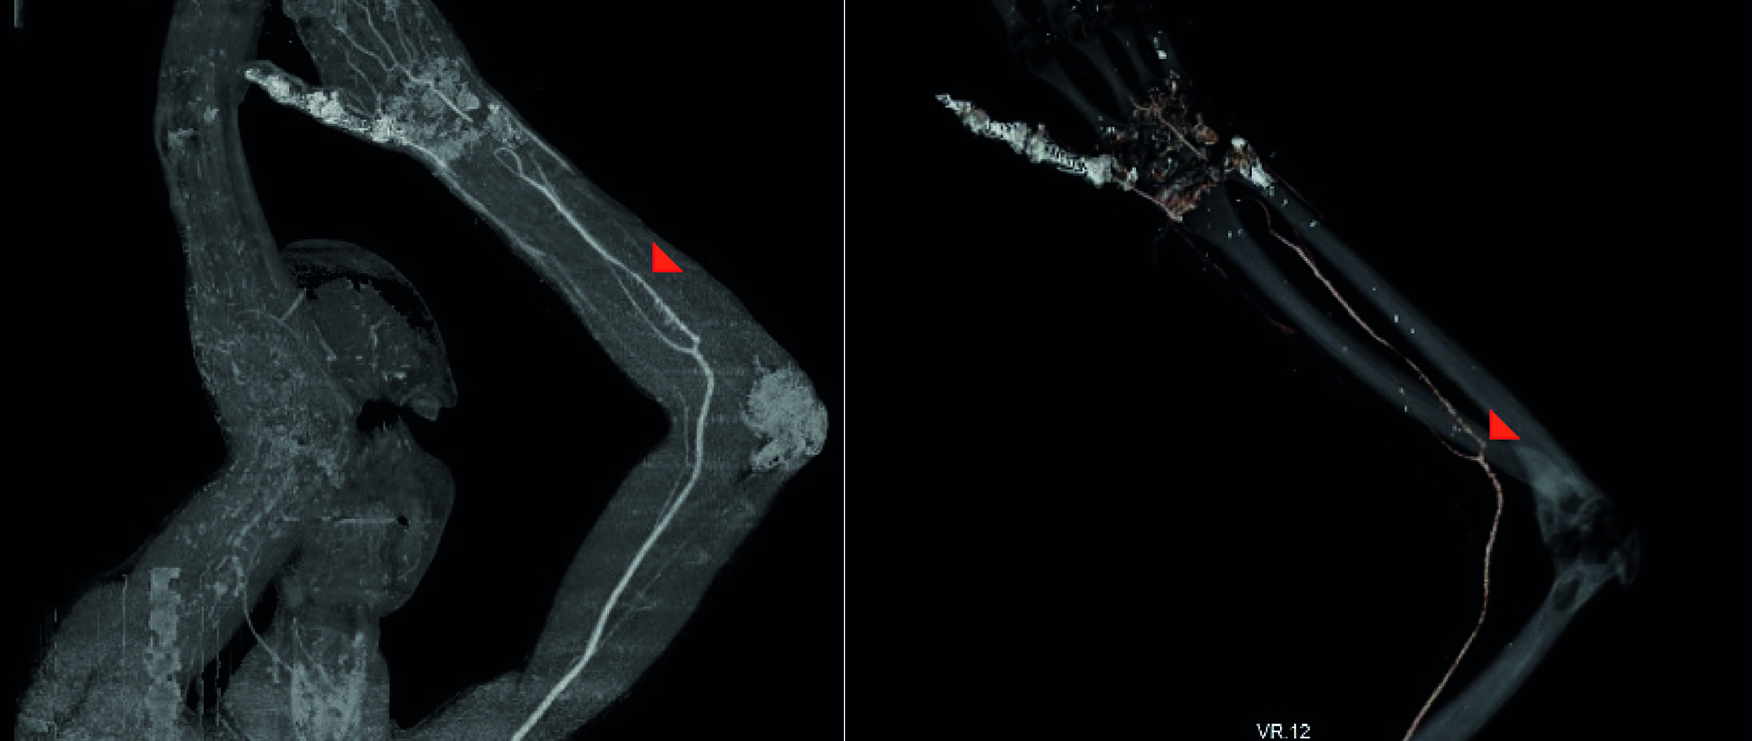

The imaging study showed a median artery originating as a continuation of the anterior interosseous artery (Figure 2) and ending in the palm with an incomplete superficial palmar arch (Figure 3). It was inferred that the preserved perfusion of the hand (Figure 4) without the need for anastomosis of the ulnar or the radial artery was secondary to the presence of the anatomical variant diagnosed in the scan (Figure 5). There was no adverse reaction to the contrast.

Figure 2 33-year-old male. A complete section of radial and ulnar arteries. A. The red arrow indicates the median artery. B. The red arrow indicates the origin of the median artery as a continuation of the anterior interosseous artery. Angiotomography. Ioversol injection. 100 mL. 3 seconds.